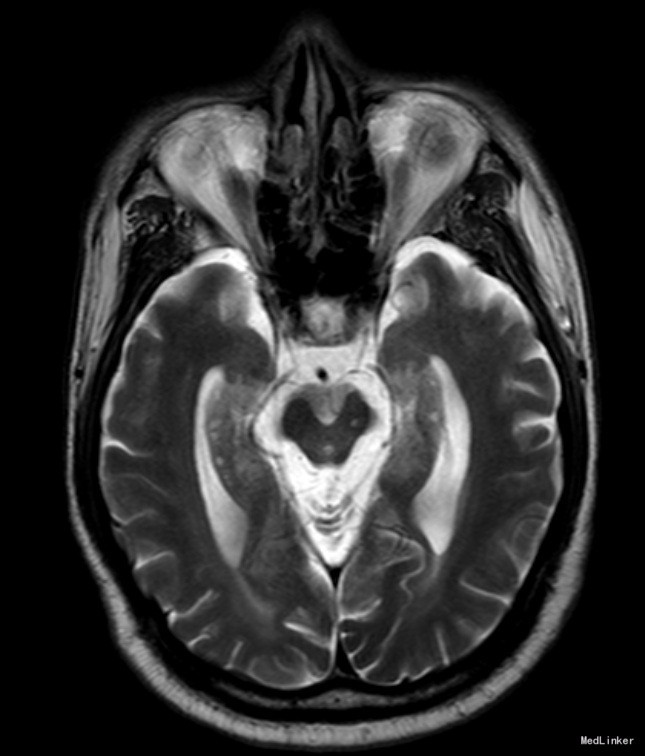

临床表现:(1)核上性眼肌麻痹:是PSP最具诊断价值的临床表现,出现早晚差异很大,一般在出现核上性眼肌麻痹时才得以诊断。早期表现为两眼追随性下视麻痹、上视受限,逐渐发展成完全性垂直凝视麻痹,晚期侧视运动亦受累。自发性凝视较追踪性凝视更易受累,但核上性眼肌麻痹常在发病多年后才出现,给早期诊断造成困难。(2)帕金森综合征症状:常对称起病,步态不稳是最常见的首发症状,尤易向后跌倒,系眼-前庭功能障碍、躯干强直、少动所致。轴性肌强直是本病的另一特征,即颈肌及上部躯干肌强直比四肢强直明显,表现为身体笔直伴颈后仰的特殊体姿。(3)假性延髓性麻痹。(4)认知功能障碍与行为异常:认知功能障碍以皮质下痴呆为特征,表现为思维缓慢、健忘伴淡漠、抑郁及执行功能减退。晚期可出现睁闭眼失用症。 MRI特征:脑MR平扫可见第三脑室和脚间池变宽、中脑和四叠体萎缩、导水管周围FLAIR像高信号等改变,还可出现不同程度大脑皮质萎缩,以额叶明显。在MR正中矢状面T1加权像平扫,PSP以中脑顶盖萎缩为主,中脑嘴明显变尖,使中脑、脑桥和小脑整体上形似蜂鸟,称为“蜂鸟征”(humming bird sign)。PSP患者MR轴位可见中脑前后径明显缩短,谓之“鼠耳征”(mouse ears sign);同时,由于中脑被盖部外侧缘凹陷,也可表现为“牵牛花征”。